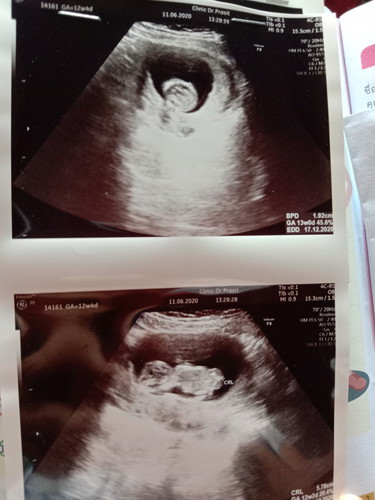

12สัปดาห์

น้องเริ่มตอดแล้วค่ะแต่แม่ๆจะยังไม่รุ้สึกเพราะน้องตอดเบามาก ไปหาหมอมาเมื่อวานหมอบอกมาค่ะและก็ซาวน์ให้ดูน้องค่ะ